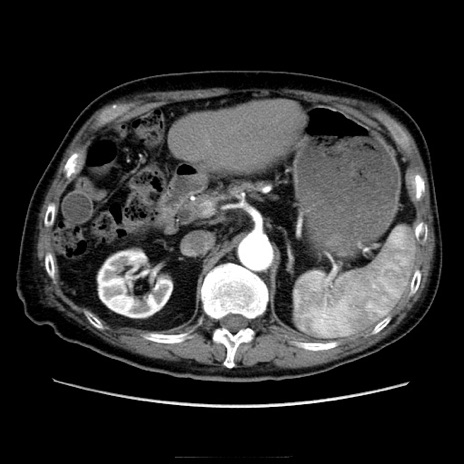

症例21(横断像)

【症例】70歳代男性

【主訴】腹痛

【現病歴】肝硬変・肝細胞癌にてかかりつけの方。約9時間前に食後より腹痛出現。症状が徐々に増悪し、嘔吐出現したため来院。

【既往歴】肝硬変、肝細胞癌(RFA、TACE後)

【身体所見】意識清明、表情苦悶様、BT 36℃、BP 129/78mmHg、P 88bpm、SpO2 97%(RA)、右上腹部から心窩部にかけて圧痛あり、反跳痛なし、筋性防御あり。

【データ】WBC 5800、CRP 0.16